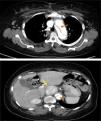

TC toracoabdominopélvica, que revelou disseção da aorta a jusante da prótese, que se estende para a aorta abdominal até à artéria ilíaca primitiva direita, sem envolvimento dos troncos supra‐aórticos e com perfusão simultânea do verdadeiro e falso lúmen; formação nodular sólida hipercaptante e ligeiramente heterogénea, bem circunscrita e com 4,5cm de maior diâmetro em topografia interaortocava e ao nível da emergência do tronco celíaco (Figura 3).